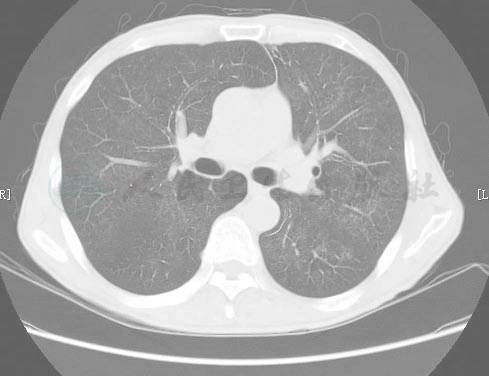

图1-1 2007年6月29日胸部CT平扫示双肺弥漫性磨玻璃样影改变,呈地图样或马赛克样分布

患者于4个月前(2007年6月28日至7月6日)曾因发热、气喘在我科住院,当时查体:颜面部见5个不规则鲜红色斑,最大约1cm×2cm,右颌下可触及一枚约花生米大小的肿大淋巴结,质中,有压痛,活动度好。双上颌窦有压痛,咽充血,扁桃体Ⅰ度肿大,所有指、趾甲呈灰白色,甲床增厚,粗糙,无光泽,余无特殊。血常规示:WBC 3.75×109/L,N 67.9%,L 15.5%,淋巴细胞绝对值明显下降(0.6×109/L);ESR107mm/h;血LDH 214.2U/L;肺部CT提示两肺弥漫分布的磨玻璃影(图1)。肺功能提示弥散功能减弱,占预计值46.5%。诊断“过敏性肺炎、支气管哮喘、急性上呼吸道感染、慢性鼻窦炎、指(趾)甲真菌感染 ”,予“左氧氟沙星、普米克令舒、可必特”等治疗,病情好转,复查胸部CT病灶见有所吸收(图2)出院。 既往1997年患“右肺浸润性结核”,抗结核治疗2年,病灶钙化治愈。有慢性鼻炎史20余年。有“磺胺”致皮疹史。无手术及外伤史,无血制品输注史。生于原籍,否认长期异地居住史及冶游史;否认有吸毒及有害物质接触史;吸烟近30年,10支/日,近5年饮白酒,每日约100ml。已婚,育有一子,爱人及儿子身体健康。

图1-2 2007年6月29日胸部CT平扫示双肺弥漫性磨玻璃样影改变,呈地图样或马赛克样分布